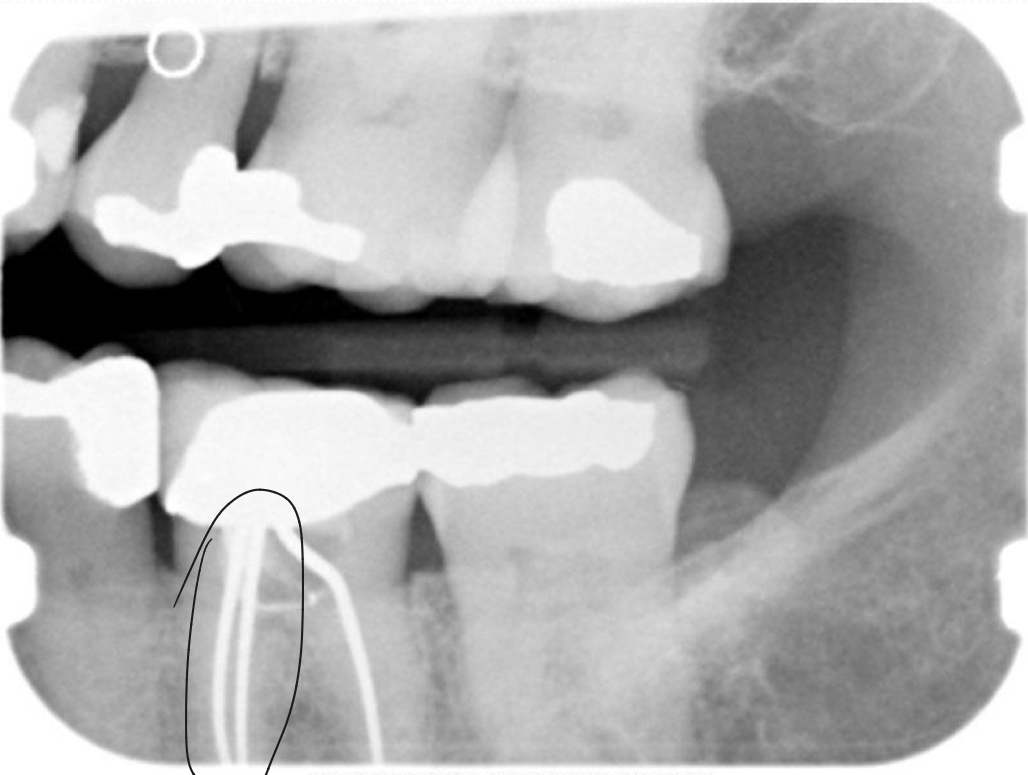

Post and core

Gutta percha

Silver points